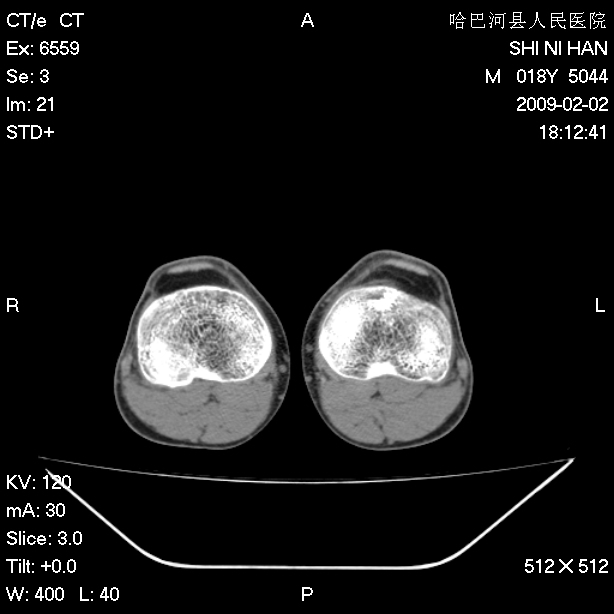

标题: CT17889:外伤后右膝关节反复疼痛3年余 [打印本页]

标题: CT17889:外伤后右膝关节反复疼痛3年余

ct未见明显异常。关节腔未见明显积液,半月板未见明显撕裂。但最好还是mri看看韧带及半月板情况。